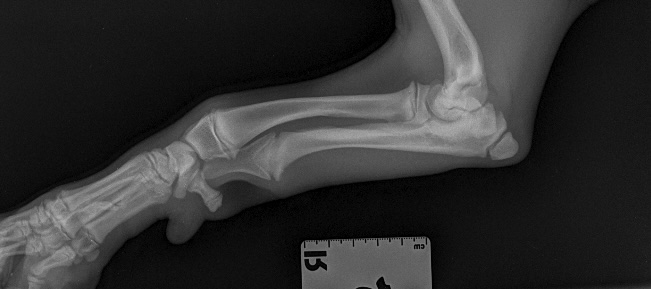

Otto is a gorgeous 14-week-old springer spaniel who very sadly broke his elbow.

This is actually quite a common fracture in young spaniels and is caused by the ‘growth plate’ of the elbow (where bones grow from in young animals) being a weak point within the joint. All Otto did was jump down from the sofa, and because of the exact force at the moment his foot hit the ground, the weight was transferred up his leg, into his elbow, through the soft growth plate and out of the side of the elbow – this is called a lateral condylar fracture.